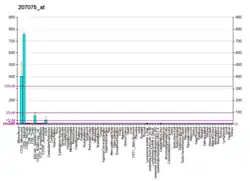

NLRP3 is expressed predominantly in macrophages and as a component of the inflammasome,[7][8]: 436 detects products of damaged cells such as extracellular ATP and crystalline uric acid. Activated NLRP3 in turn triggers an immune response. Mutations in the NLRP3 gene are associated with a number of organ specific autoimmune diseases.

NLRP3 is a component of the innate immune system that functions as a pattern recognition receptor (PRR) that recognizes pathogen-associated molecular patterns (PAMPs).[14] NLRP3 belongs to the NOD-like receptor (NLR) subfamily of PRRs and NLRP3 together with the adaptor ASC protein PYCARD forms a caspase-1 activating complex known as the NLRP3 inflammasome. NLRP3 in the absence of activating signal is kept in an inactive state complexed with HSP90 and SGT1 in the cytoplasm. NLRP3 inflammasome detects danger signals such as crystalline uric acid and extracellular ATP released by damaged cells. These signals release HSP90 and SGT1 from and recruit ASC protein and caspase-1 to the inflammasome complex. Caspase-1 within the activated NLRP3 inflammasome complex in turn activates the inflammatory cytokine, IL-1β.[14]